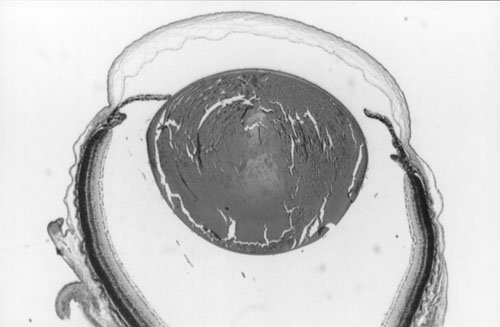

Figure 2. Histology of Ccw/+ eyes

A. Normal littermate 10 days post partum. B. Ccw/+ 10 days post partum. Some vacuolation of the lens is visible. C. Ccw/+ 20 days post partum. Lens fibers are becoming swollen and disorganized. D. Ccw/+ 4-6 weeks post partum. Lens fibers are largely degraded. E. Ccw/+ 14 weeks post partum. Only the lens capsule and some epithelium remain.

A.